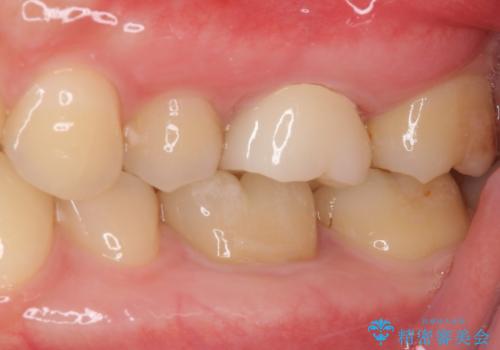

- 奥歯の銀歯の下にあるむし歯治療を希望して来院された患者様です。

口を開けたときに見えてしまう部分はセラミックインレーやジルコニアクラウンに、目立たない部分はゴールドインレーにてむし歯治療を行うこととしました。

機能面を優先すると、PGAインレー(ゴールドインレー)による修復治療やPGAクラウンによる補綴治療が望ましいのですが、笑ったときに見えている銀歯がどうしても気なってしまうとのことで、目立ってしまう奥歯はセラミックインレーやセラミッククラウンを装着することとしました。

見た目を気にすることなくむし歯治療を行うことができ、患者様に大変満足していただきました。